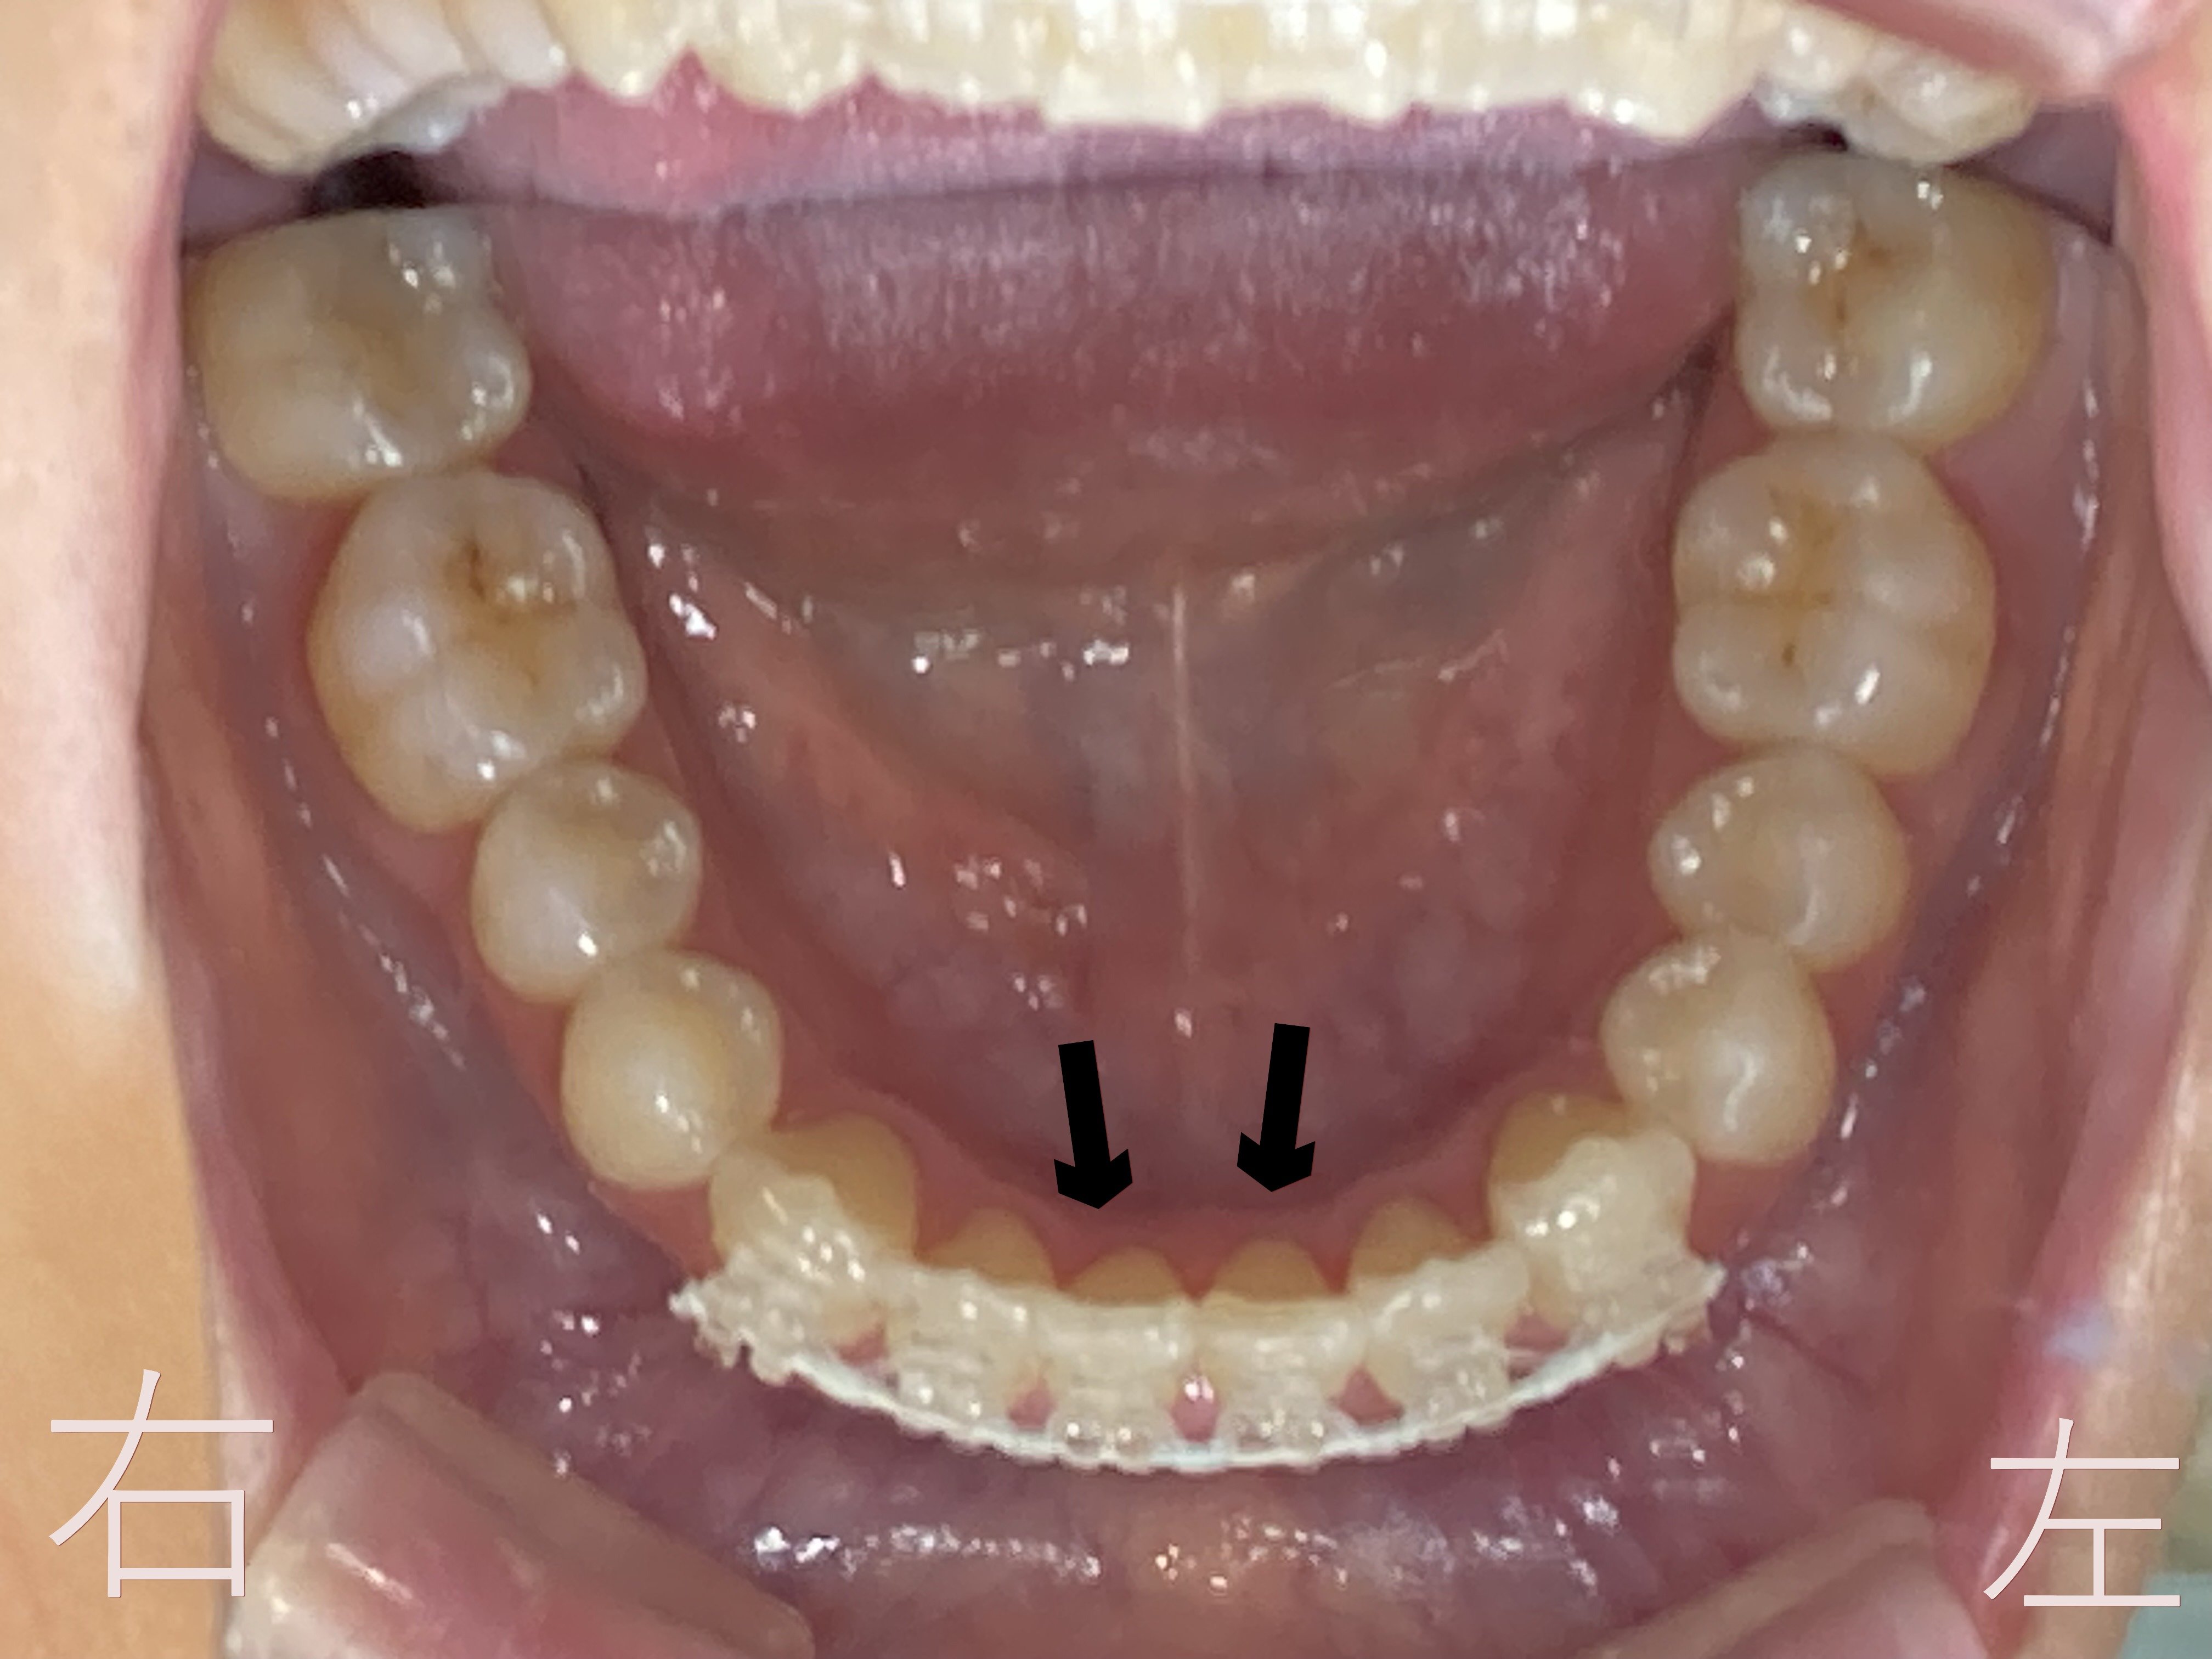

上記写真をご覧ください。下顎前歯部(黒色矢印)に歯のゆがみ【叢生】が認められます。

上記は8か月後の下顎の咬合面観です。黒色矢印の下顎前歯(黒色矢印の部分)のゆがみ【叢生】が解消されているのが確認できます。

上記はボタン(マルチブラケット)を外した後の下顎左右前歯部(黒色矢印)の口腔内写真です。

下顎前歯部のゆがみ【叢生】が解消していることが確認できます。